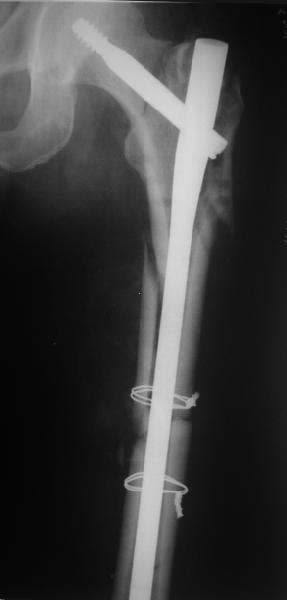

В общем, сделали. См. приложение.

Длина и из-за этого ось получились не совсем такие, как хотелось бы, все-таки срок после той операции уже 6 недель. Может быть, стоило провести дистракцию аппаратом неделю-другую. Заранее спасибо за комментарии и критику.

Наверное так и надо сделать. Будет непросто предотвратить при введении смещение Гаммы кнаружи через имеющийся дефект кортикала. Уверен, Александр Николоевич, Вы с эти справитесь. Удачи!

Александр, поздравляю от души, отличная работа, вообще-то и у меня тоже были опасения по поводу латеральной стенки. Идеальное показаниt к применению импланта закрытым методом при таких переломах, когда болт замыкается в штифте, конструкции придается угловая жесткость, примерно как в Blade Plate.